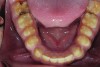

Figure 7. Preoperative mandibular occlusal view.

Figure 7